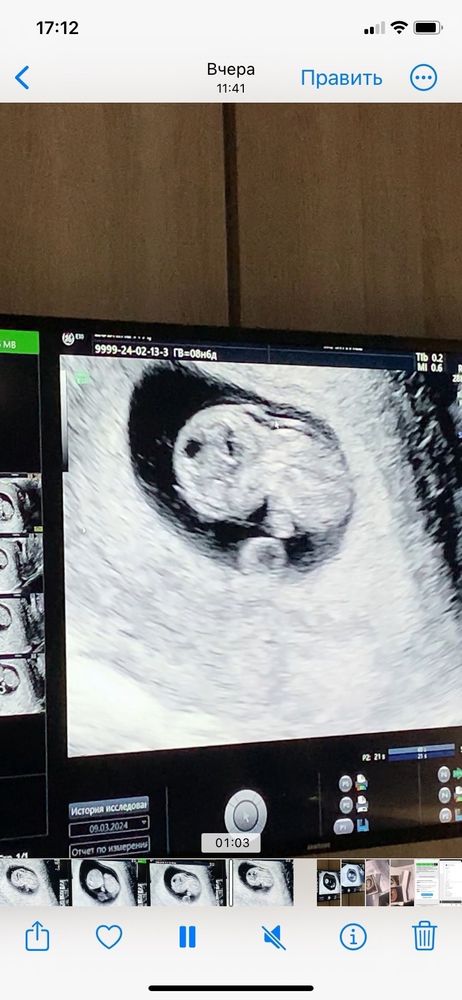

Узи 9 недель

Не паникуйте. Не понимаю врача, которая Вас напугала на таком сроке. ТВП измеряется ТОЛЬКО сроке 12 недель, т.е. на первом скрининга. Также ТВП смотрят вместе с КТР, если уже ТВП больше 3 будет на скрининге, тогда уже стоит дальше обследоваться и искать причину. Сейчас Вам просто бессмысленно измерили ТВП и напугали, успокойтесь и ждите скрининга. Хорошей беременности🌸

На первых фото его видно, но главное размер.